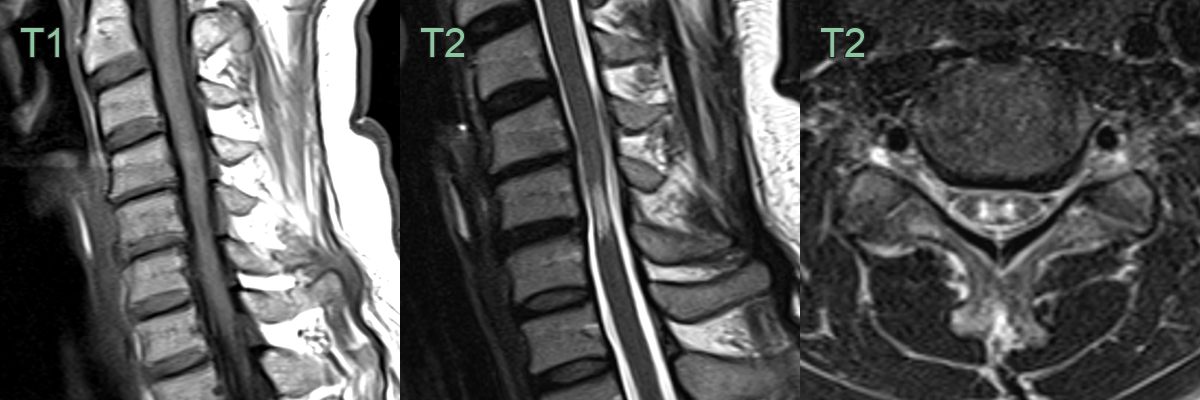

- Magnetic Resonance Imaging (MRI):

- Gold standard for diagnosis

- T2-weighted images: hyperintense signal within the cord

- T1-weighted images: assess for cord atrophy

- Gadolinium-enhanced T1: evaluate for tumours or infection